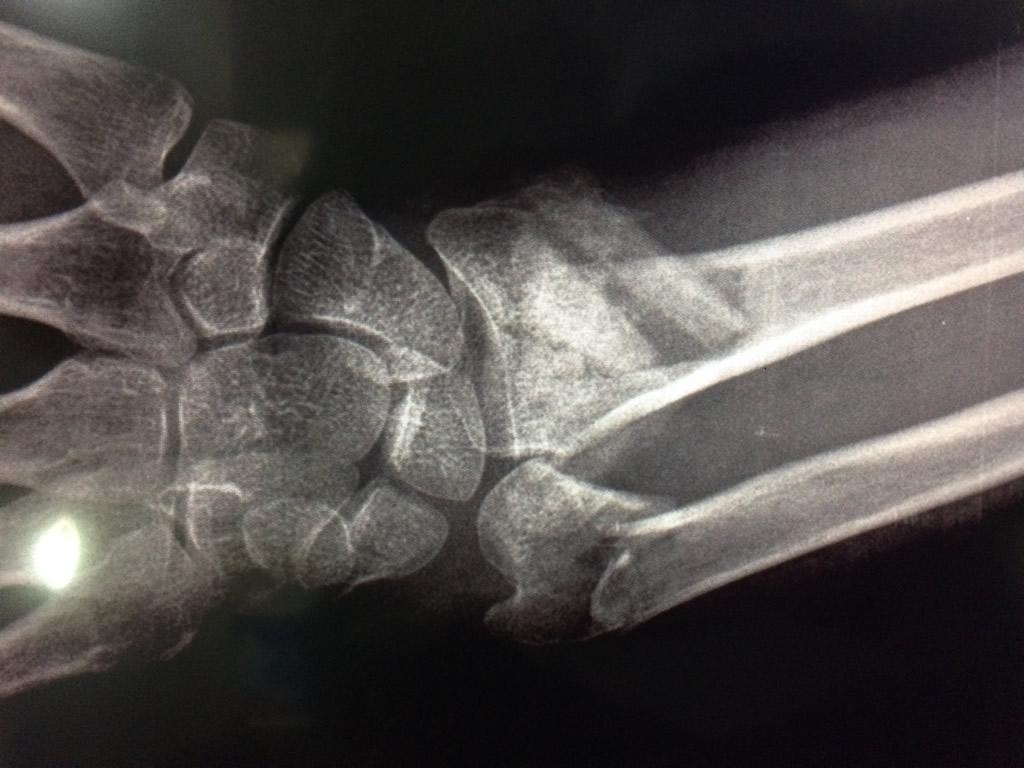

Cirugías de Muñecas

Los procedimientos más comunes en cirugía de la mano son aquellos destinados a reparar traumatismos, incluyendo lesiones de tendones, nervios, vasos sanguíneos, y articulaciones; huesos fracturados; y quemaduras, cortes, y otros daños de la piel.